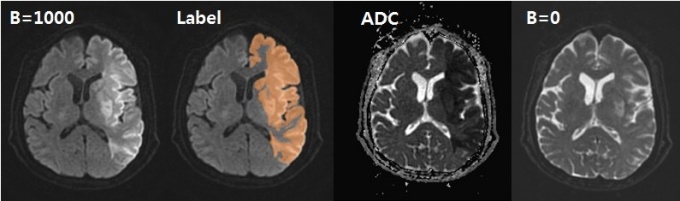

Àα׷¡µð¾ðÆ®´Â ´ë±¸°¡Å縯´ëÀÇ·á¿ø ºòµ¥ÀÌÅÍ ÀΰøÁö´É¼¾ÅÍ À±¼º¿ø ±³¼öÆÀ°ú ÇÔ²² '±Þ¼º ³úÁ¹Áß º´º¯ ÀÚµ¿ ŽÁö¿Í ºÐȹȭ¸¦ À§ÇÑ È®»ê°­Á¶ ³ú MRI µ¥ÀÌÅͼ Á¦ÀÛ ¹× ÀΰøÁö´É °³¹ß' °úÁ¦¸¦ ¼öÇàÇÑ´Ù.

À̹ø °úÁ¦·Î ±Þ¼º ³úÁ¹Áß¿¡ ´ëÇÑ µö·¯´× ±â¼ú Àû¿ë ¹× ¿µ»óÀÇÇÐÀû ÆÇµ¶À» º¸Á¶ÇÒ ¼ö ÀÖ´Â ¼Ö·ç¼ÇÀ» °³¹ßÇÒ ¿¹Á¤ÀÌ´Ù.

ƯÈ÷ °³¹ßÇÑ ¼Ö·ç¼ÇÀº ±Þ¼º³úÁ¹Áß º´º¯ À¯¹«·¹üÀ§·ºÎÇÇ·Å©±â È®Àΰú ÆÇµ¶ ¾÷¹« ¼Óµµ ÁõÁø, Áø·á ¼º°ø·üÀ» ³ôÀ̴µ¥ ±â¿©ÇÒ °ÍÀ¸·Î ±â´ëÇϰí ÀÖ´Ù.